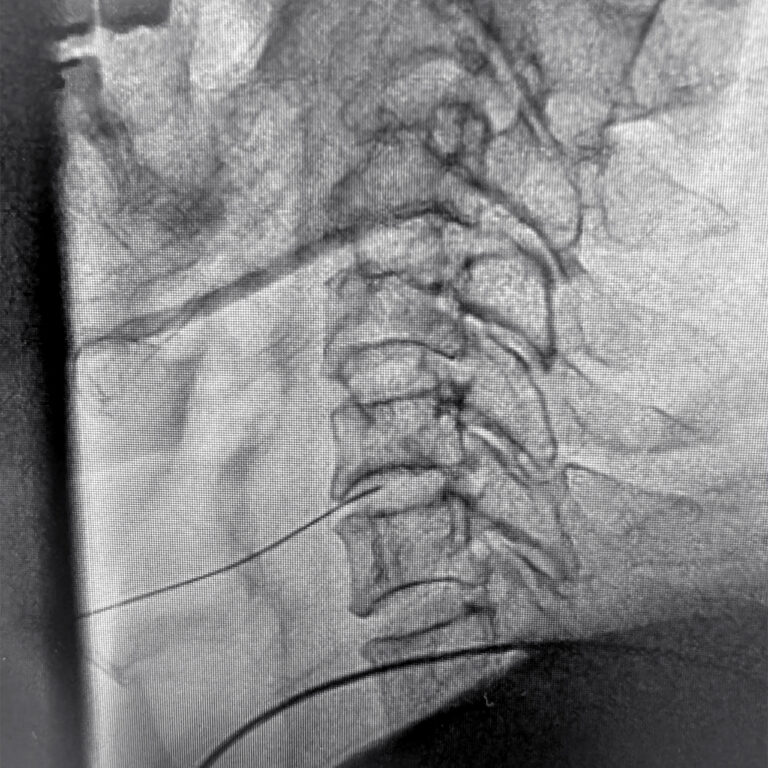

当院の日帰り腰痛治療では主に「椎間板」を治療しています。椎間板とは腰骨を支えるクッションのような働きがあります。その組織内にはゼリー状の「髄核(ずいかく)」があり、中の髄核を覆う線維の束のように「線維輪(せんいりん)」があります。

この線維輪に損傷する(傷がつく)と、中から髄核が漏れ出し、椎間板ヘルニアや脊柱管狭窄症等の病気の原因になります。当院では腰の病気の原因となる椎間板を治療することで、腰痛や坐骨神経痛等の症状を改善させることを目的としています。